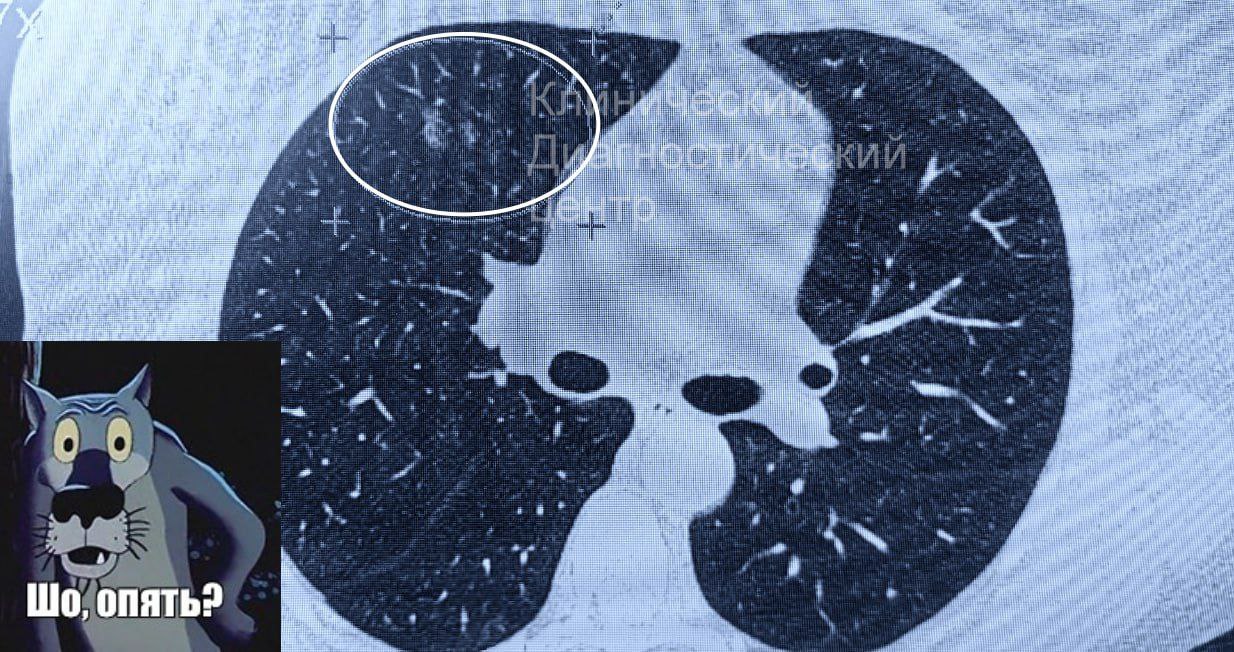

Это атипичная микоплазменная пневмония, которая вызывает эффект «матового стекла», он заметен на снимке КТ лёгких.

Что-то на ковидном — у нижегородцев стали диагностировать коварную патологию.